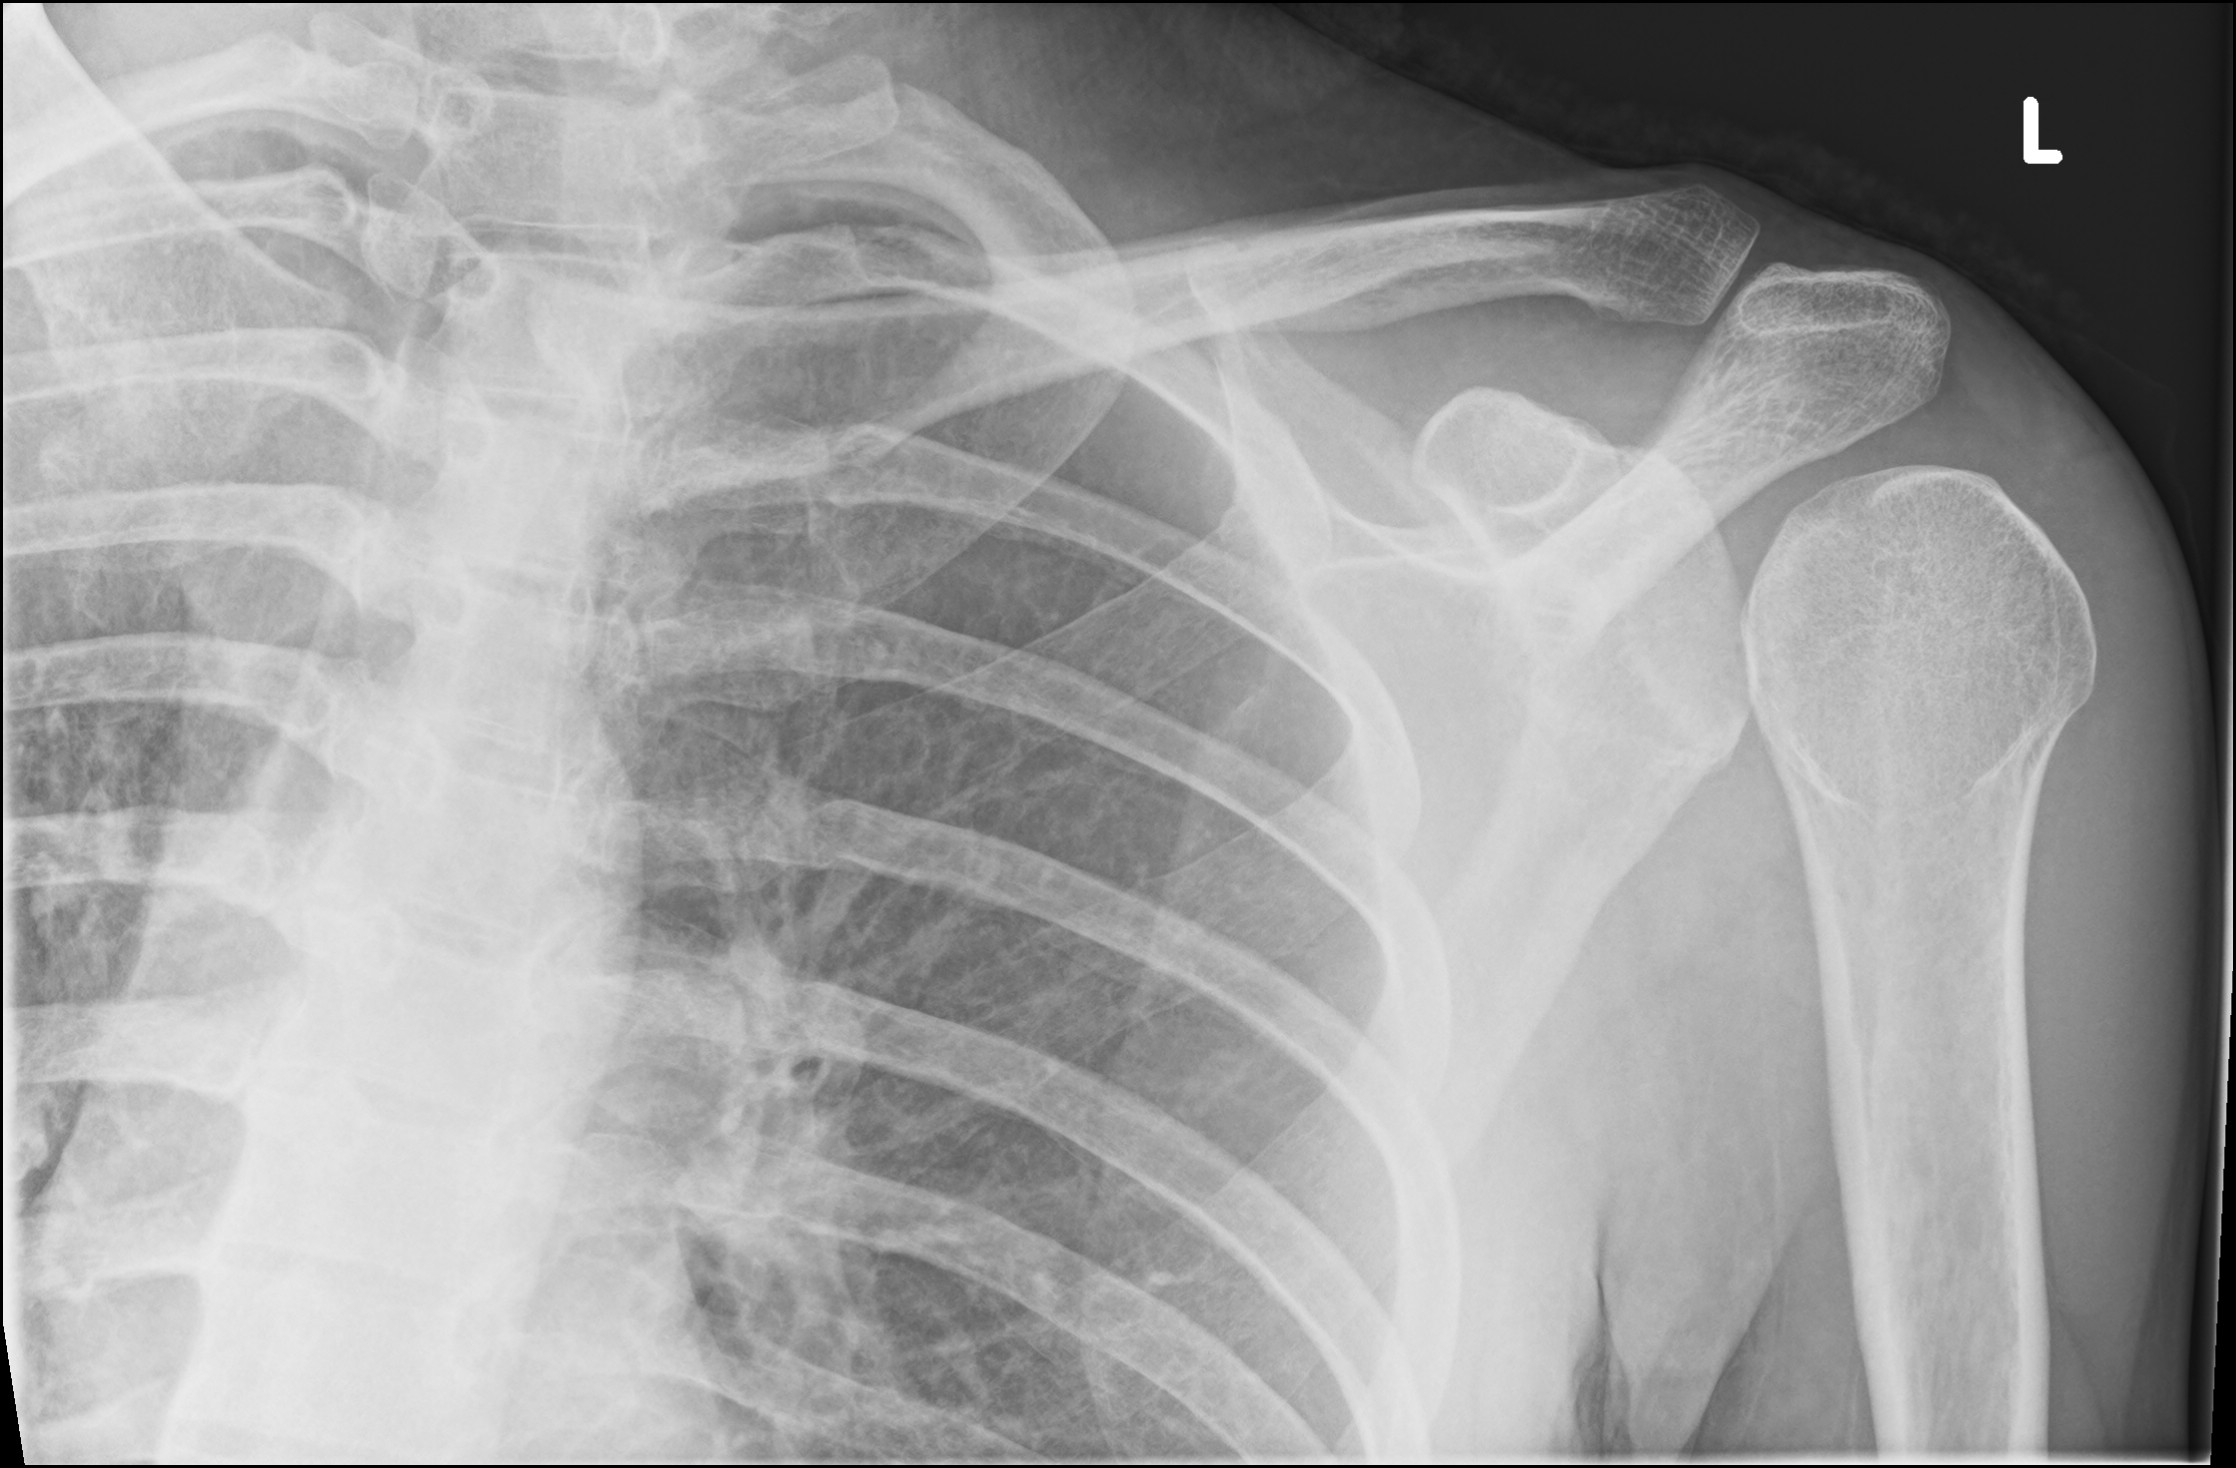

| Diagnostic investigations | XR appearance: humeral head lying anteroinferior to glenoid |

Source: https://radiopaedia.org/cases/anterior-shoulder-dislocation-26?lang=gb

https://radiopaedia.org/cases/anterior-shoulder-dislocation-37?lang=gb